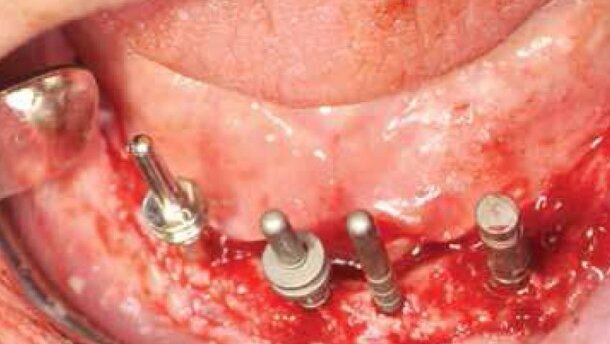

Pacjent został znieczulony przewodowo 4% artycainą z noradrenaliną, a następnie odsłonięto płat śluzówkowo-okostnowy (Ryc. 4). Ze względu na położenie otworów bródkowych blisko szczytu wyrostka zębodołowego, zostały one całkowicie odsłonięte a ich położenie dla lepszej orientacji oznaczono tymczasowo pinami tytanowymi (Ryc. 5).

Implantację rozpoczęto w 4. kwadrancie. W trakcie przygotowywania łoża implantów (Ryc. 6 i 7) wykonano kontrolne zdjęcia radiologiczne ze znacznikami głębokości (Ryc. 8). W pierwszej kolejności nawiercono kość na głębokość 4 mm, wykonano kontrolne badanie rtg, a następnie pogłębiono do 6 mm. Postępowanie takie było konieczne ze względu na bliskość kanału żuchwy.

Następnie łoża implantów poszerzono do odpowiedniej średnicy i wszczepiono 2 implanty Straumann® SP, Ø 4.1 mmRN, SLActive® 6 mm.

W kolejnym etapie przygotowano łoża implantów w odcinku przednim (Ryc. 9) oraz wszczepiono implanty okolicy zębów 31, 41, 42 i 43 Straumann® NNC, SLActive® 12 mm, TiZr (Ryc. 10-12). W odcinku przednim zdecydowano o zastosowaniu w/w implantów ze względu na wąski wyrostek zębodołowy przy jednoczesnym zachowaniu ich bardzo dużej wytrzymałości mechanicznej. Implanty NNC wykonane ze stopu tytanowo-cyrkonowego znanego pod nazwą Roxolid® mimo średnicy 3,3 mm posiadają wytrzymałość większą od implantów standardowych o średnicy 4.1 mm.